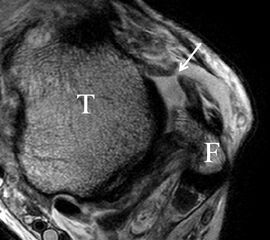

Man unterscheidet bei dem Ligamentum deltoideum eine tiefe Schicht (Pars tibiotalare posterior, Pars tibiotalare anterius) und eine oberflächliche Schicht (Pars tibionaviculare, Pars tibiocalcaneare, Pars tibiotalare posterius superficialis und Tibiospring-Ligament) 10. Hochauflösende Techniken lassen eine differenzierte Beurteilung aller Bandanteile zu. Sowohl rein ligamentäre als auch osteo-ligamentäre Ausrisse sind normalerweise gut zu erkennen. Die Pars tibiotalaris posterior ist multifaszikulär aufgebaut und sowohl axial als auch coronar (Abb. 19 a) gut bildgebend abzugrenzen. Die deutlich kleinere, nur inkonstant angelegte Pars tibiotalare anterior inseriert an einem kleinen Talustuberkel (Abb. 19 b). Ossäre Bandausrisse kommen hier gehäuft vor. Proximal verlaufen die Pars tibiocalcaneare und die Pars tibionaviculare gemeinsam (Abb. 19 c) nach kaudal und trennen sich dann in zum Calcaneus und zum Os naviculare ziehende Bündel auf. Ein besonderer Typ ligamentärer Verbindungen stellt das Tibiospring-Ligament dar. Es verbindet nicht wie für Ligamente typisch zwei Knochen miteinander, sondern es hat seinen ossären Ursprung an der Tibia und inseriert am Pfannenband (Ligamentum calcaneonaviculare plantare, im englischen Schrifttum Spring-Ligament genannt), also nicht ossär. Das Innenband ist mit 60% der Verletzungen am häufigsten betroffen. Isolierte Innenbandverletzungen sind jedoch selten. Sie treten gehäuft assoziiert mit Syndesmosenläsionen, Fibulafrakturen, Verletzungen des Muskulus tibialis posterior und des Pfannenbandes auf (H.-K. Beyer 2003). Entsprechend sollte auf diese Kollateralverletzungen bei der Beurteilung geachtet werden. Eine weitere Folge von Verletzungen des Ligamentum deltoideum ist die chronische Sprunggelenksinstabilität. Arthroskopisch weisen hier bis zu 40% der Patienten einen elongierten Verlauf des Ligamentum deltoideum auf. In diesem Patientenkollektiv besteht auch eine erhöhte chondrale Komorbidität mit arthroskopisch erkennbaren Knorpelschäden (98%) im Gegensatz zu der Patientengruppe (66% Knorpelschäden) mit reiner Außenbandinstabilität 11. Dies belegt die klinische Bedeutung von Innenbandverletzungen.